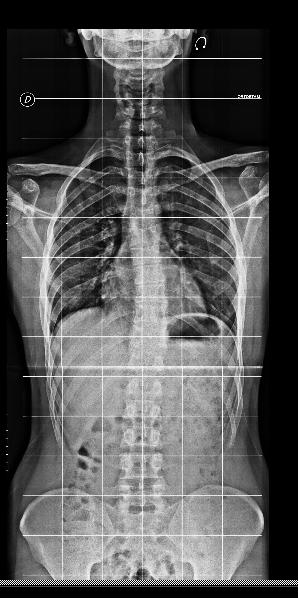

Mi hanno consigliato questo esercizio in sostituzione del lento avanti, in quanto sconsigliato per chi ha problemi di scoliosi. Al momento non riesco a fare più di un piegamento che sia decente, quindi sto cercando di tenere semplicemente la posizione verticale il più possibile per sviluppare un po' di forza per arrivare a fare qualche piegamento decente, come un'esercizio isometrico insomma (al momento circa 30 secondi per 5 volte).